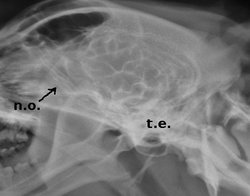

Los nervios ópticos (n.o.) y el quiasma óptico (q.o) se pueden observar en una ventriculografía (radiografía con contraste yodado aplicado en cisterna magna). Recordemos que los nervios ópticos están envueltos por meninges y por ende por líquido cefalorraquídeo.

Es fácil visualizar en la ventriculografía también el tronco encefálico (t.e)